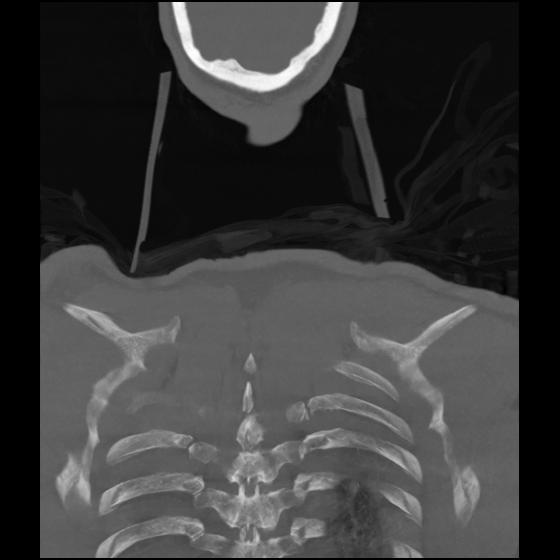

23 ANGIO,CE,Cor-MIP,5.000,ANGIO,Cor-MIP,